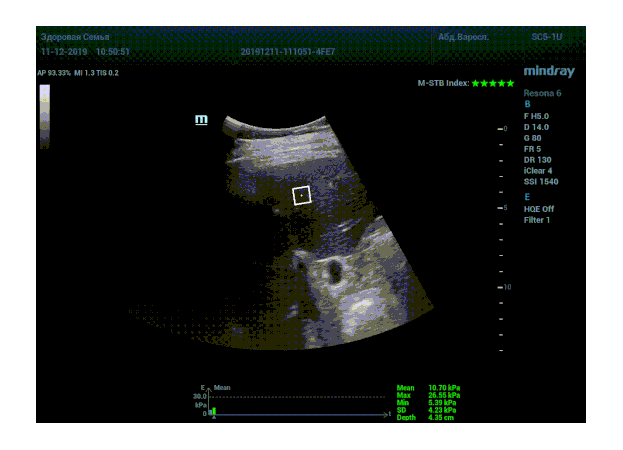

Что может дать ультразвуковое исследование печени помимо образований, гепатомегалии и цирроза? Диагностические системы, оснащенные функцией STQ (SoundTouchQuantification) имеют возможность регистрировать сдвиговые волны в паренхиме печени и оценить её эластичность. Такие возможности есть у систем серии Resona 6 и Resona 7 компании Mindray.

Определение плотности печени. Не ошибся ли оператор при измерении эластических свойств печени? Для оценки критериев качества предусмотрен индекс MBT, который покажет насколько «твердой» была рука оператора и двигалась ли печень. При MBT 5* рука тверда и показатели достоверны. Для оценки качества результатов используется IQR индекс, отображающий колебания показателей в точке измерения при расчете медианы. Показатели при IQR <30% считаются приемлемыми. Техника сканирования через межреберные промежутки требует размещение окна интереса на несколько сантиметром ниже капсулы, для исключения эффекта реверберации. Установка ROI на паренхиму без захвата сосудов, для исключения погрешностей измерения.

Стадия фиброза определяется по системе METAVIR Staging, построенной на данных биопсии и сопоставлении с данными эластографии. Своевременная диагностика фиброза, и начало его лечения, залог благоприятного исхода заболевания.